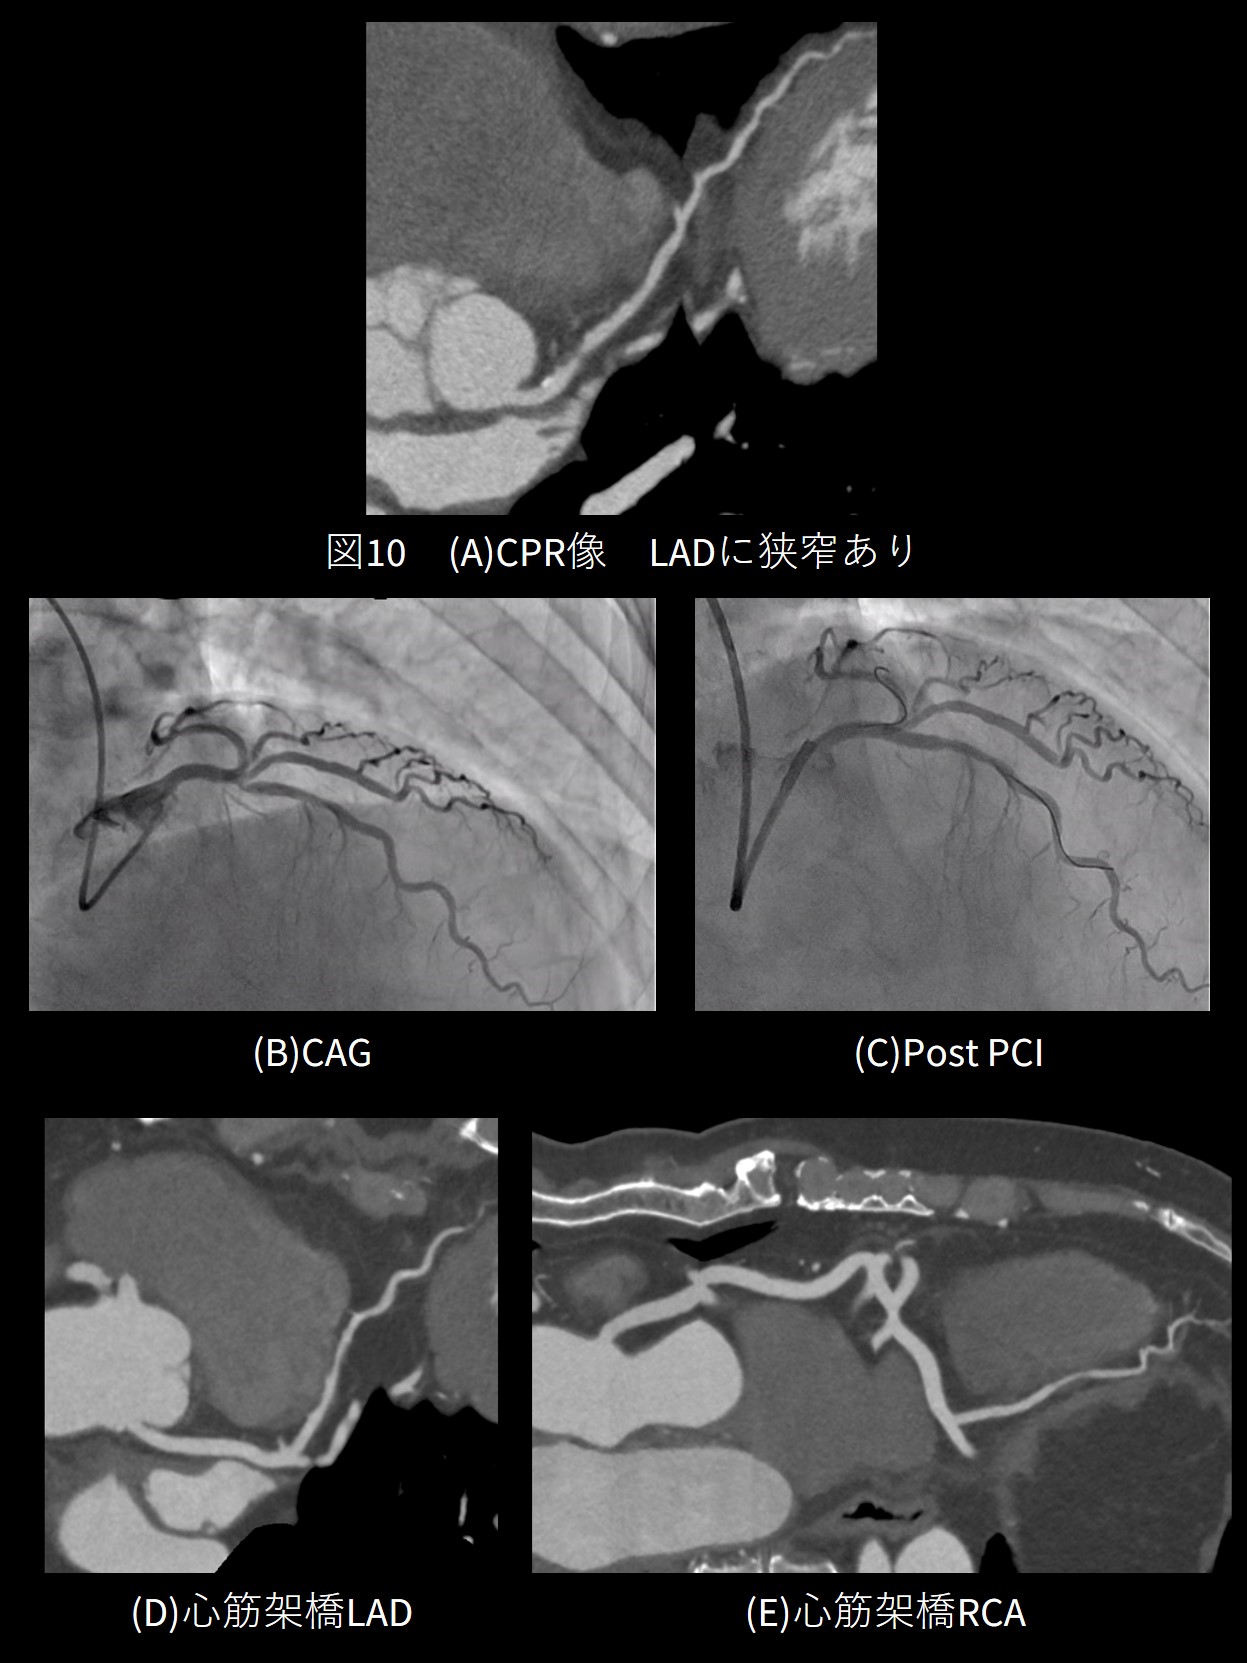

カテーテル検査を行った2例のうち1例はCCTAと同様に狭窄を認めPCIとなりました。もう1例は冠動脈の一部が心筋組織に圧排されることによって血流障害を起こす心筋架橋でした。拡張期の一部で冠動脈が狭窄してしまうように見えてしまう病変でしたが、その一瞬をとらえられたことにSnapShot Freeze2.0の性能の高さを改めて実感させられた症例となりました。